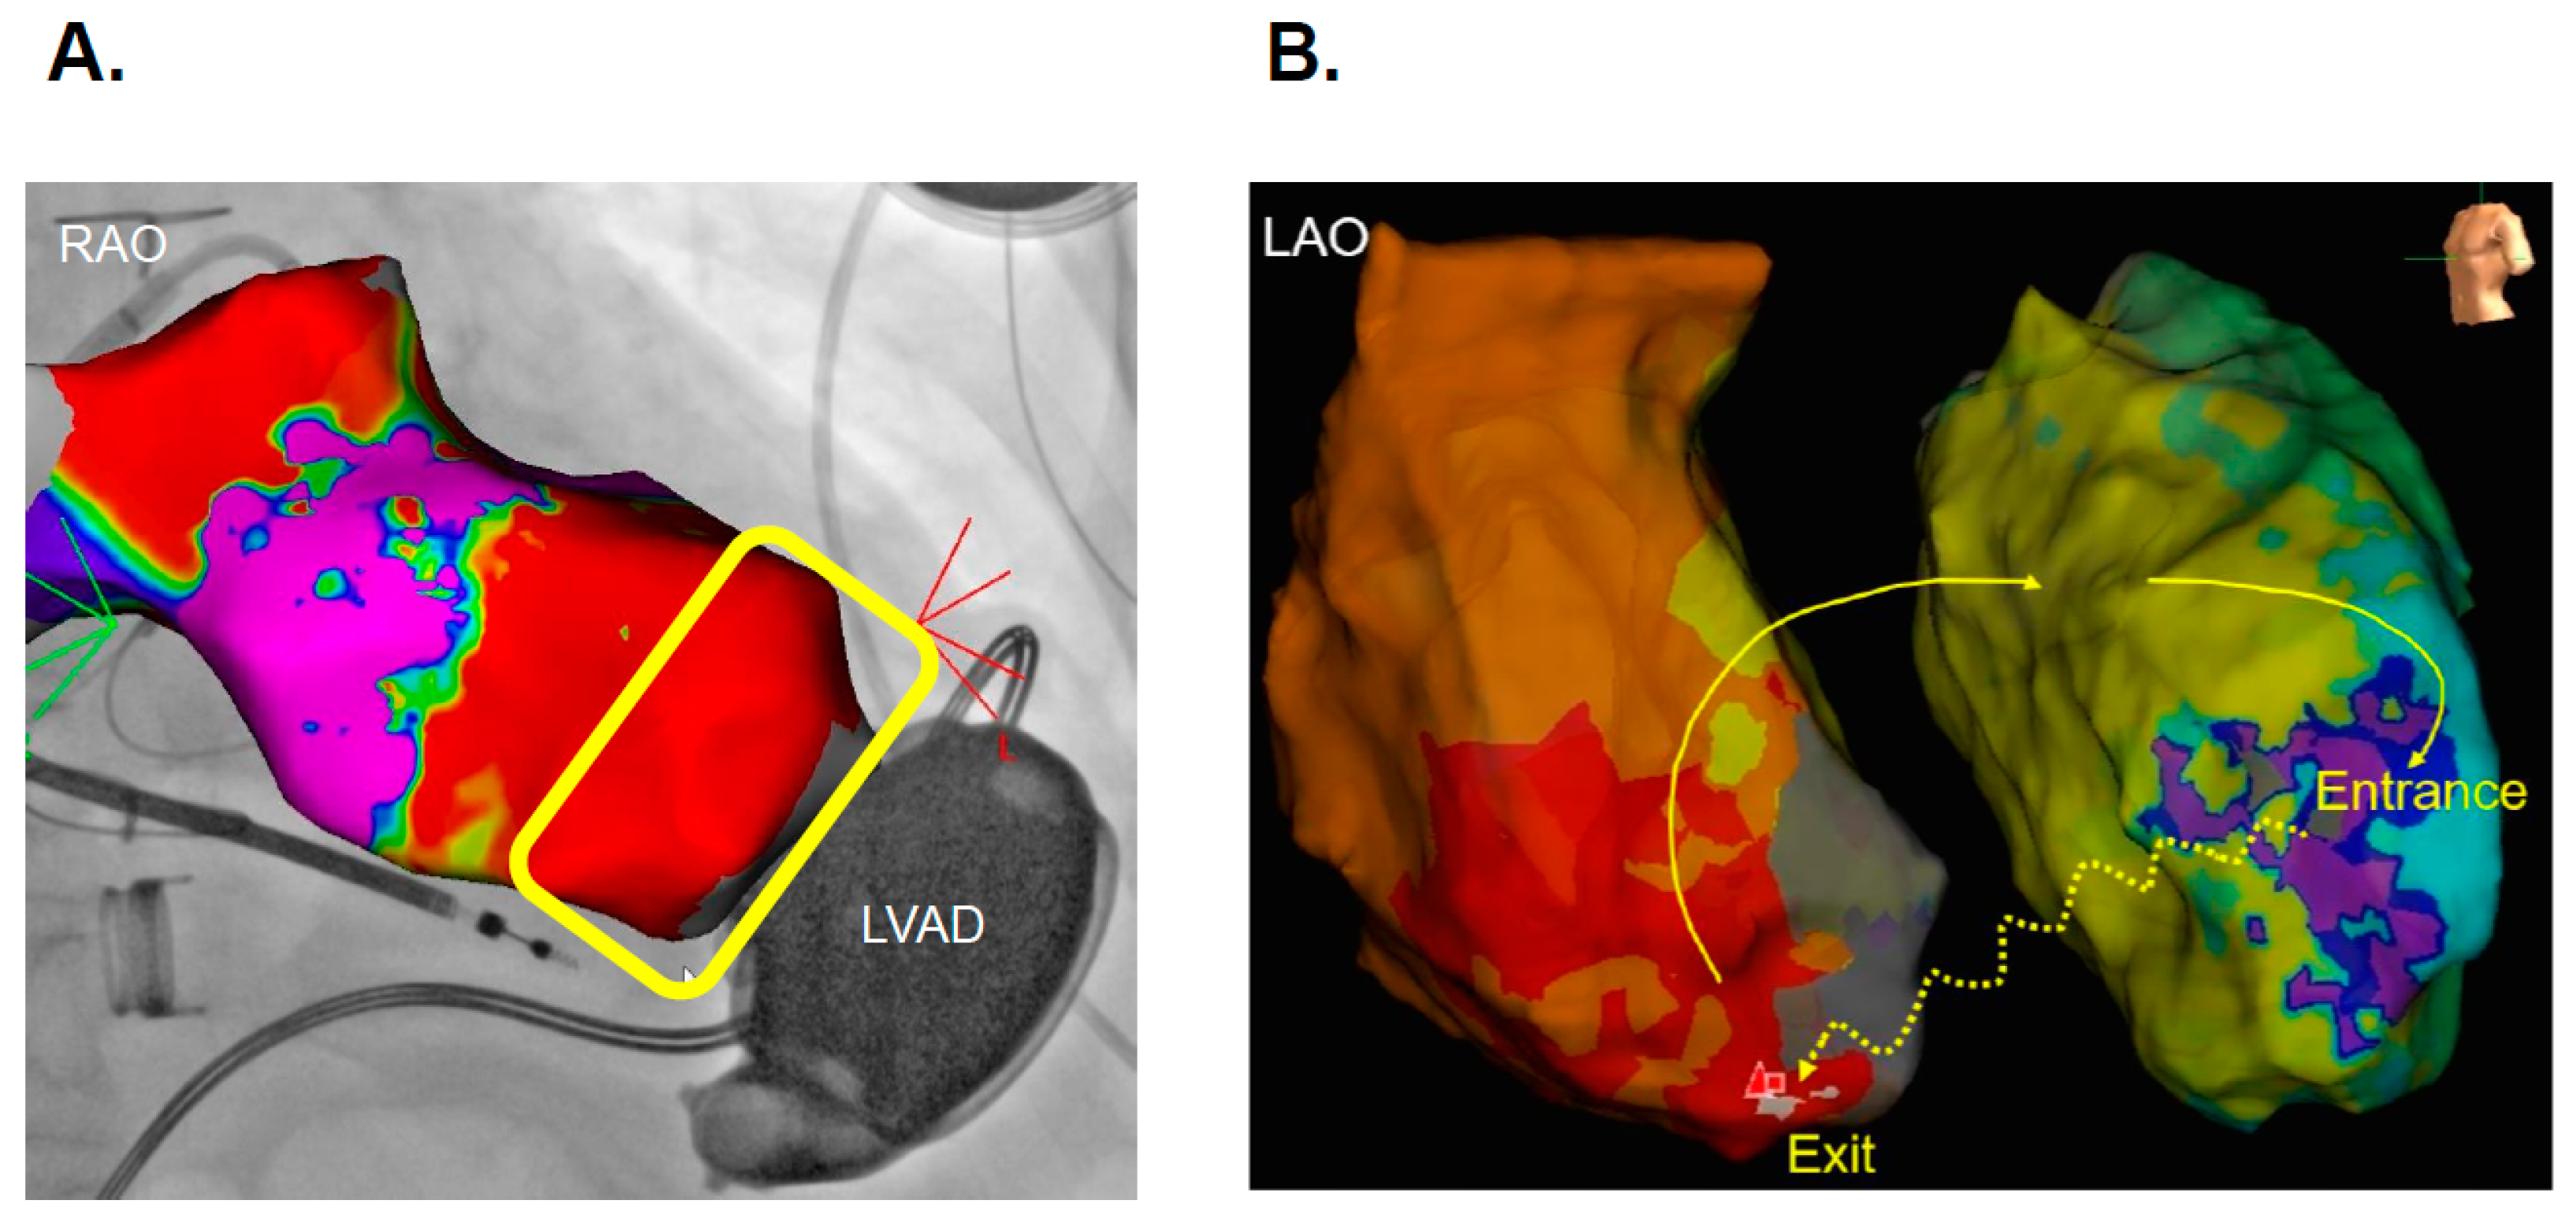

- Izumida, T.; Kataoka, N.; Imamura, T.; Uchida, K.; Koi, T.; Nakagaito, M.; Nakamura, M.; Komatsu, Y.; Nogami, A.; Kinugawa, K. Bail-out Ablation of Ventricular Tachycardia Electrical Storm in a Patient with a Durable Left Ventricular Assist Device. Intern. Med. 2023, 62, 2201–2204. [Google Scholar] [CrossRef]